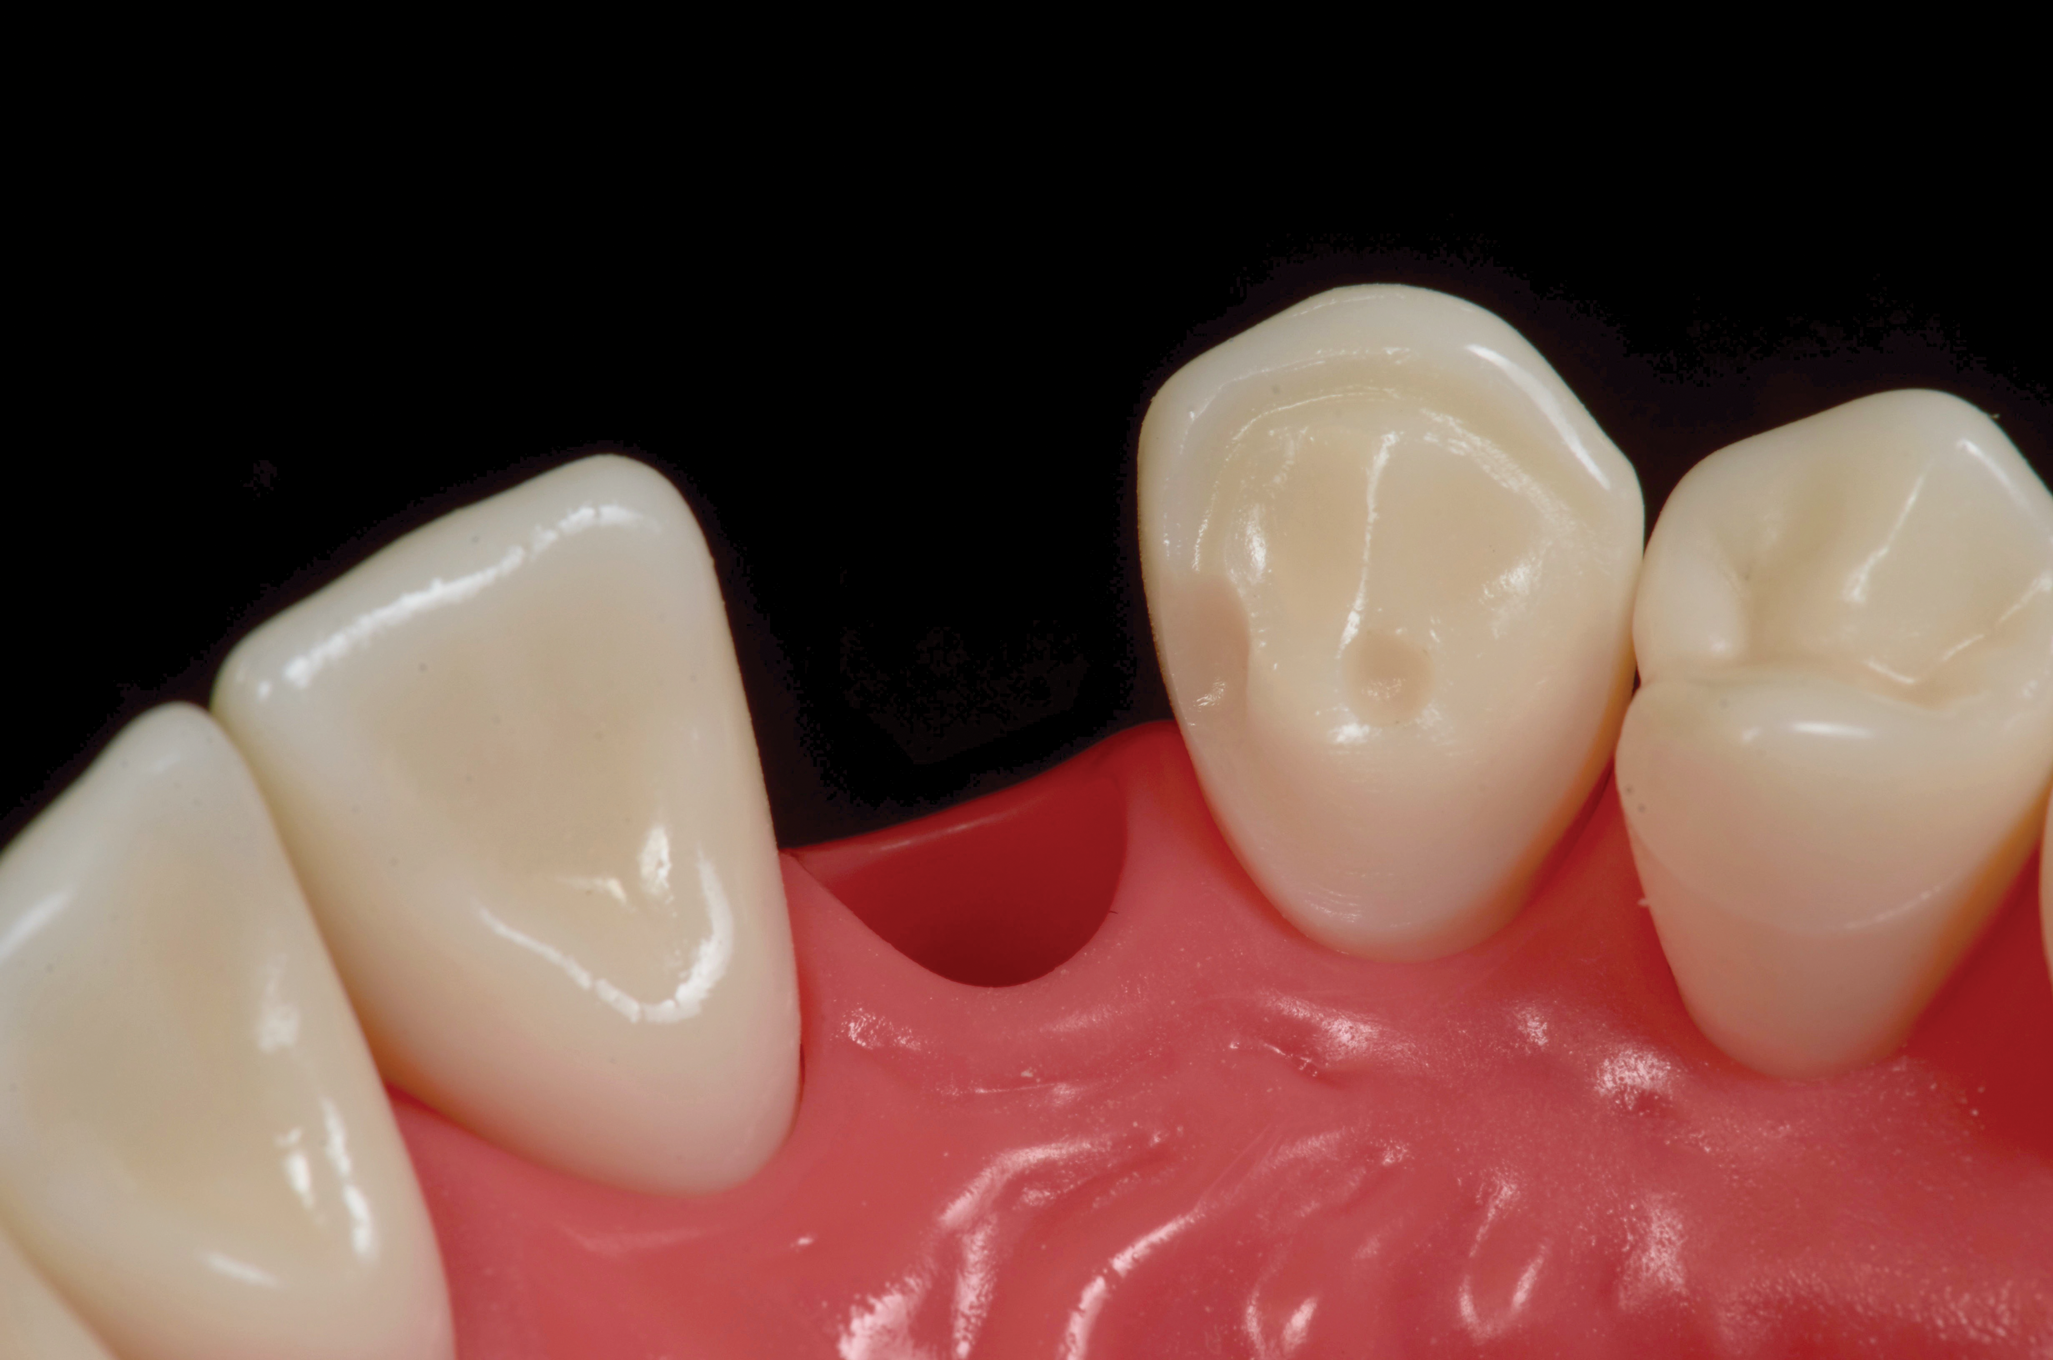

Fig 15. Four-year postoperative photograph of zirconia bonded bridge replacing tooth No. 7.

Figure 15

Fig 16. Occlusal view of the zirconia bonded bridge in Fig 15 at 4-year postoperative showing one wing on the canine abutment and a small anti-rotation extension from the pontic onto the distolingual surface of tooth No. 8.

Figure 16

There are a number of requirements to achieve a successful bonded bridge. First, the edentulous site must be approximately the same width as the contralateral tooth. There also must be adequate soft tissue to provide esthetic emergence contours for the ovate pontic. Some clinicians may be concerned that the ovate pontic will not adequately maintain the soft tissue and, over time, the tissue will shrink away from the pontic. However, the soft tissue under an ovate pontic has been shown to be quite stable long-term.39 An example of this is shown in Figure 15.

Additionally, to accomplish a bonded bridge, the abutment tooth must be large enough to provide 30 mm2 of enamel surface and a 3 mm connector height.40 The zirconia wing must be at least 0.7 mm thick to provide the required strength.40 Ideally, this space is created orthodontically to ensure there will be minimal reduction of the lingual enamel. For long-term success, the abutment must be bonded to an enamel substrate.

Next, the pontic must have resistance to facial displacement. This is accomplished by adding a slight extension on the pontic adjacent to an unbonded tooth; this will prevent the pontic from moving facially when loaded from the lingual (Figure 16). There should be no preparation on the unbonded tooth, nor should the extension be bonded so flossing may be easily accomplished. There must also be resistance form on the abutment, which can be best achieved with a vertical groove or box on the lateral surface of the abutment, adjacent to the edentulous site (Figure 17).29 There should be no excursive contacts on the pontic. Lastly, an evidence-based bonding protocol is essential for long-term success.